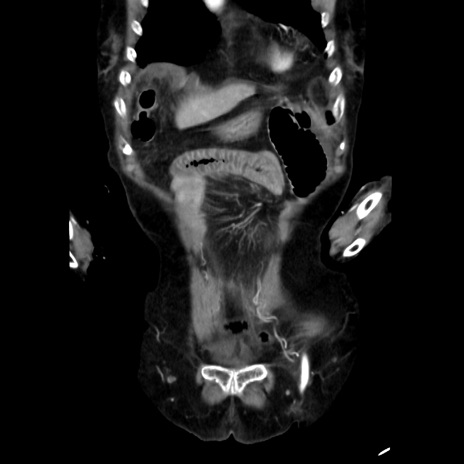

症例40(冠状断像)

【症例】90歳代女性

【主訴】腹痛・嘔吐

【現病歴】 食欲低下、嘔吐があり昨日他院受診。肺炎と診断され入院となる。入院後より腹部全体に圧痛あり。胃管留置され経過みていたが、症状持続するため、

当院転院となる。

【既往歴】胸椎圧迫骨折、胆石症

【身体所見】腹部:中央に激痛あり、圧痛あり、反跳痛不明

【データ】WBC 17100、CRP 18.82

冠状断像